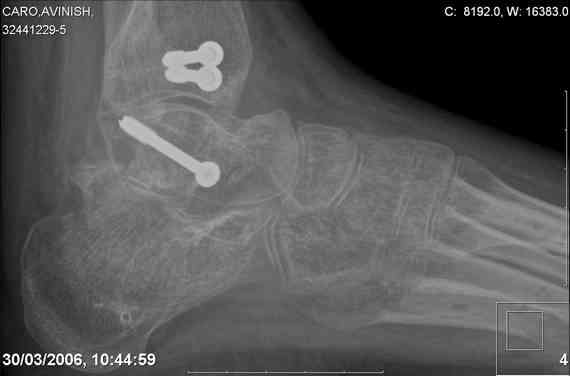

ya by popytalsya sobrat talus anatomichno,seichas pozdno operirovat iz za oteka,po etomy distrakziya apparatom budet optmalna.Posyalu vam podobyai moi sluchai.

Mark, судя по снимкам в день поступления произведен А.В.Ф., а остеосинтез ч-з какое время произведен?, остеосинтез произвели открытым способом?( на снимке п/о рубцы).

aparat postavlen v den postupleniya,rastaynuli, vpravili zakryto naskolko vozmoghno, a kogda otek spal sdelali otkrytoe vpravlenie.Teryat tut nechego, moghno tolko uluchshit.

Udachi.

Mark Eidelman